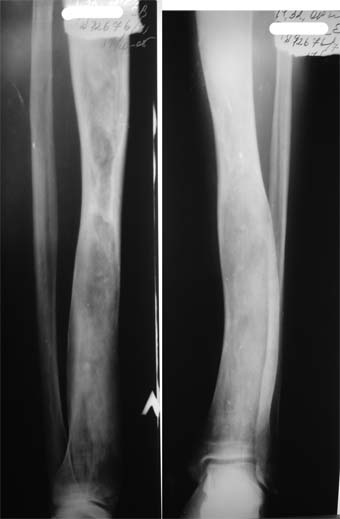

Коллеги!Пациент Д., 35 лет, В 1985 году был поставлен диагноз гемигипоплазия правой нижней конечности. Укорочение 5 см, в 1987 году остеотомия правого бедра, аппарат 4 месяца, удлинили на 2 см из-за нагноения спиц аппарат сняли. В настоящее время Жалобы на дискомфорт, тяжесть в левом бедре, голени при длительной ходьбе, при длительном лежании на левом бедре. Эти жалобы беспокоят втечение 5-6 лет. В 1999 году выявили "изменения" (со слов больного, выписки нет на руках) бедренной кости и костей голени слева. Тогда же предложили в ЦИТО срочно делать какую-то операцию. При осмотре: Правая нижняя конечность. Имеются рубцы на правом бедре по наружной и внутренней поверхностям. Ограничения движений в коленном суставе нет. Кровоснабжение, иннервация сохранены. Левая нижняя конечность. Левое бедро увеличено в объеме, при пальпации пальпируется бедренная кость большего диаметра по сравнению с левым бедром. Пальпация безболезненна. Голень обычной формы. Объем движений в суставах полный. Кровоснабжение, иннервация сохранены. Имеется разница в длине конечностей правая короче на 4-5 см за счет бедра и голени. В приложении вид больного и рентгенограммы бедра 2001 год и 2005 год. Что бы это могло быть? О чем можно думать? Онкология? С уважением Коробушкин Глеб Владимирович Российский государственный медицинский университет кафедра травматологии, ортопедии и ВПХ, доцент

В настоящее время имеется умеренный рубцовый процесс правого бедра не мешающий на объем движений в суставах. В коленном суставе слева бедро обычное, голень - булавовидное утолщение проксимального конца большеберцовой кости. На рентгенограммах тотальное поражение кости с увлечением в процесс проксимального эпиметафиза, поражение характерно для болезни Campanatsehi

У больного полиоссальноая форма фиброзной дисплазии с поражение левой бедренной и большеберцовой кости. На рентгенограммах - тотальное разрастание и остончение кортикального слоя. Имеется удлинение левой нижней конечности на 2,5-3 см за счет голени. Больному показано оперативное лечение левой большеберцовой кости.

Остеосклеротическая стадия болезни Педжета. Имею двух подобных больных по 15 -20 лет наблюдения. В острой стадии - текли как классическая саркома. "За" - все (рентген+биопсия+клиника) - отправили хоронить, а в результате живы и имеют рентген-картинку похожую Вашей. Поройтесь в минеральном обмене и в почках. Удлинять подобные кости опасно. Можно -биопсию на всякий случай (из зоны склероза и зоны пороза).